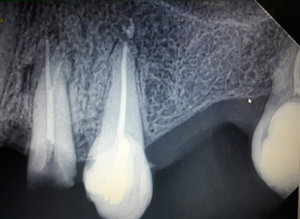

Уважаемая Мария, этот снимок немного не информативный, множество наложений и теней. Я вам рекомендую приехать на очный прием и я вам все подробно расскажу.